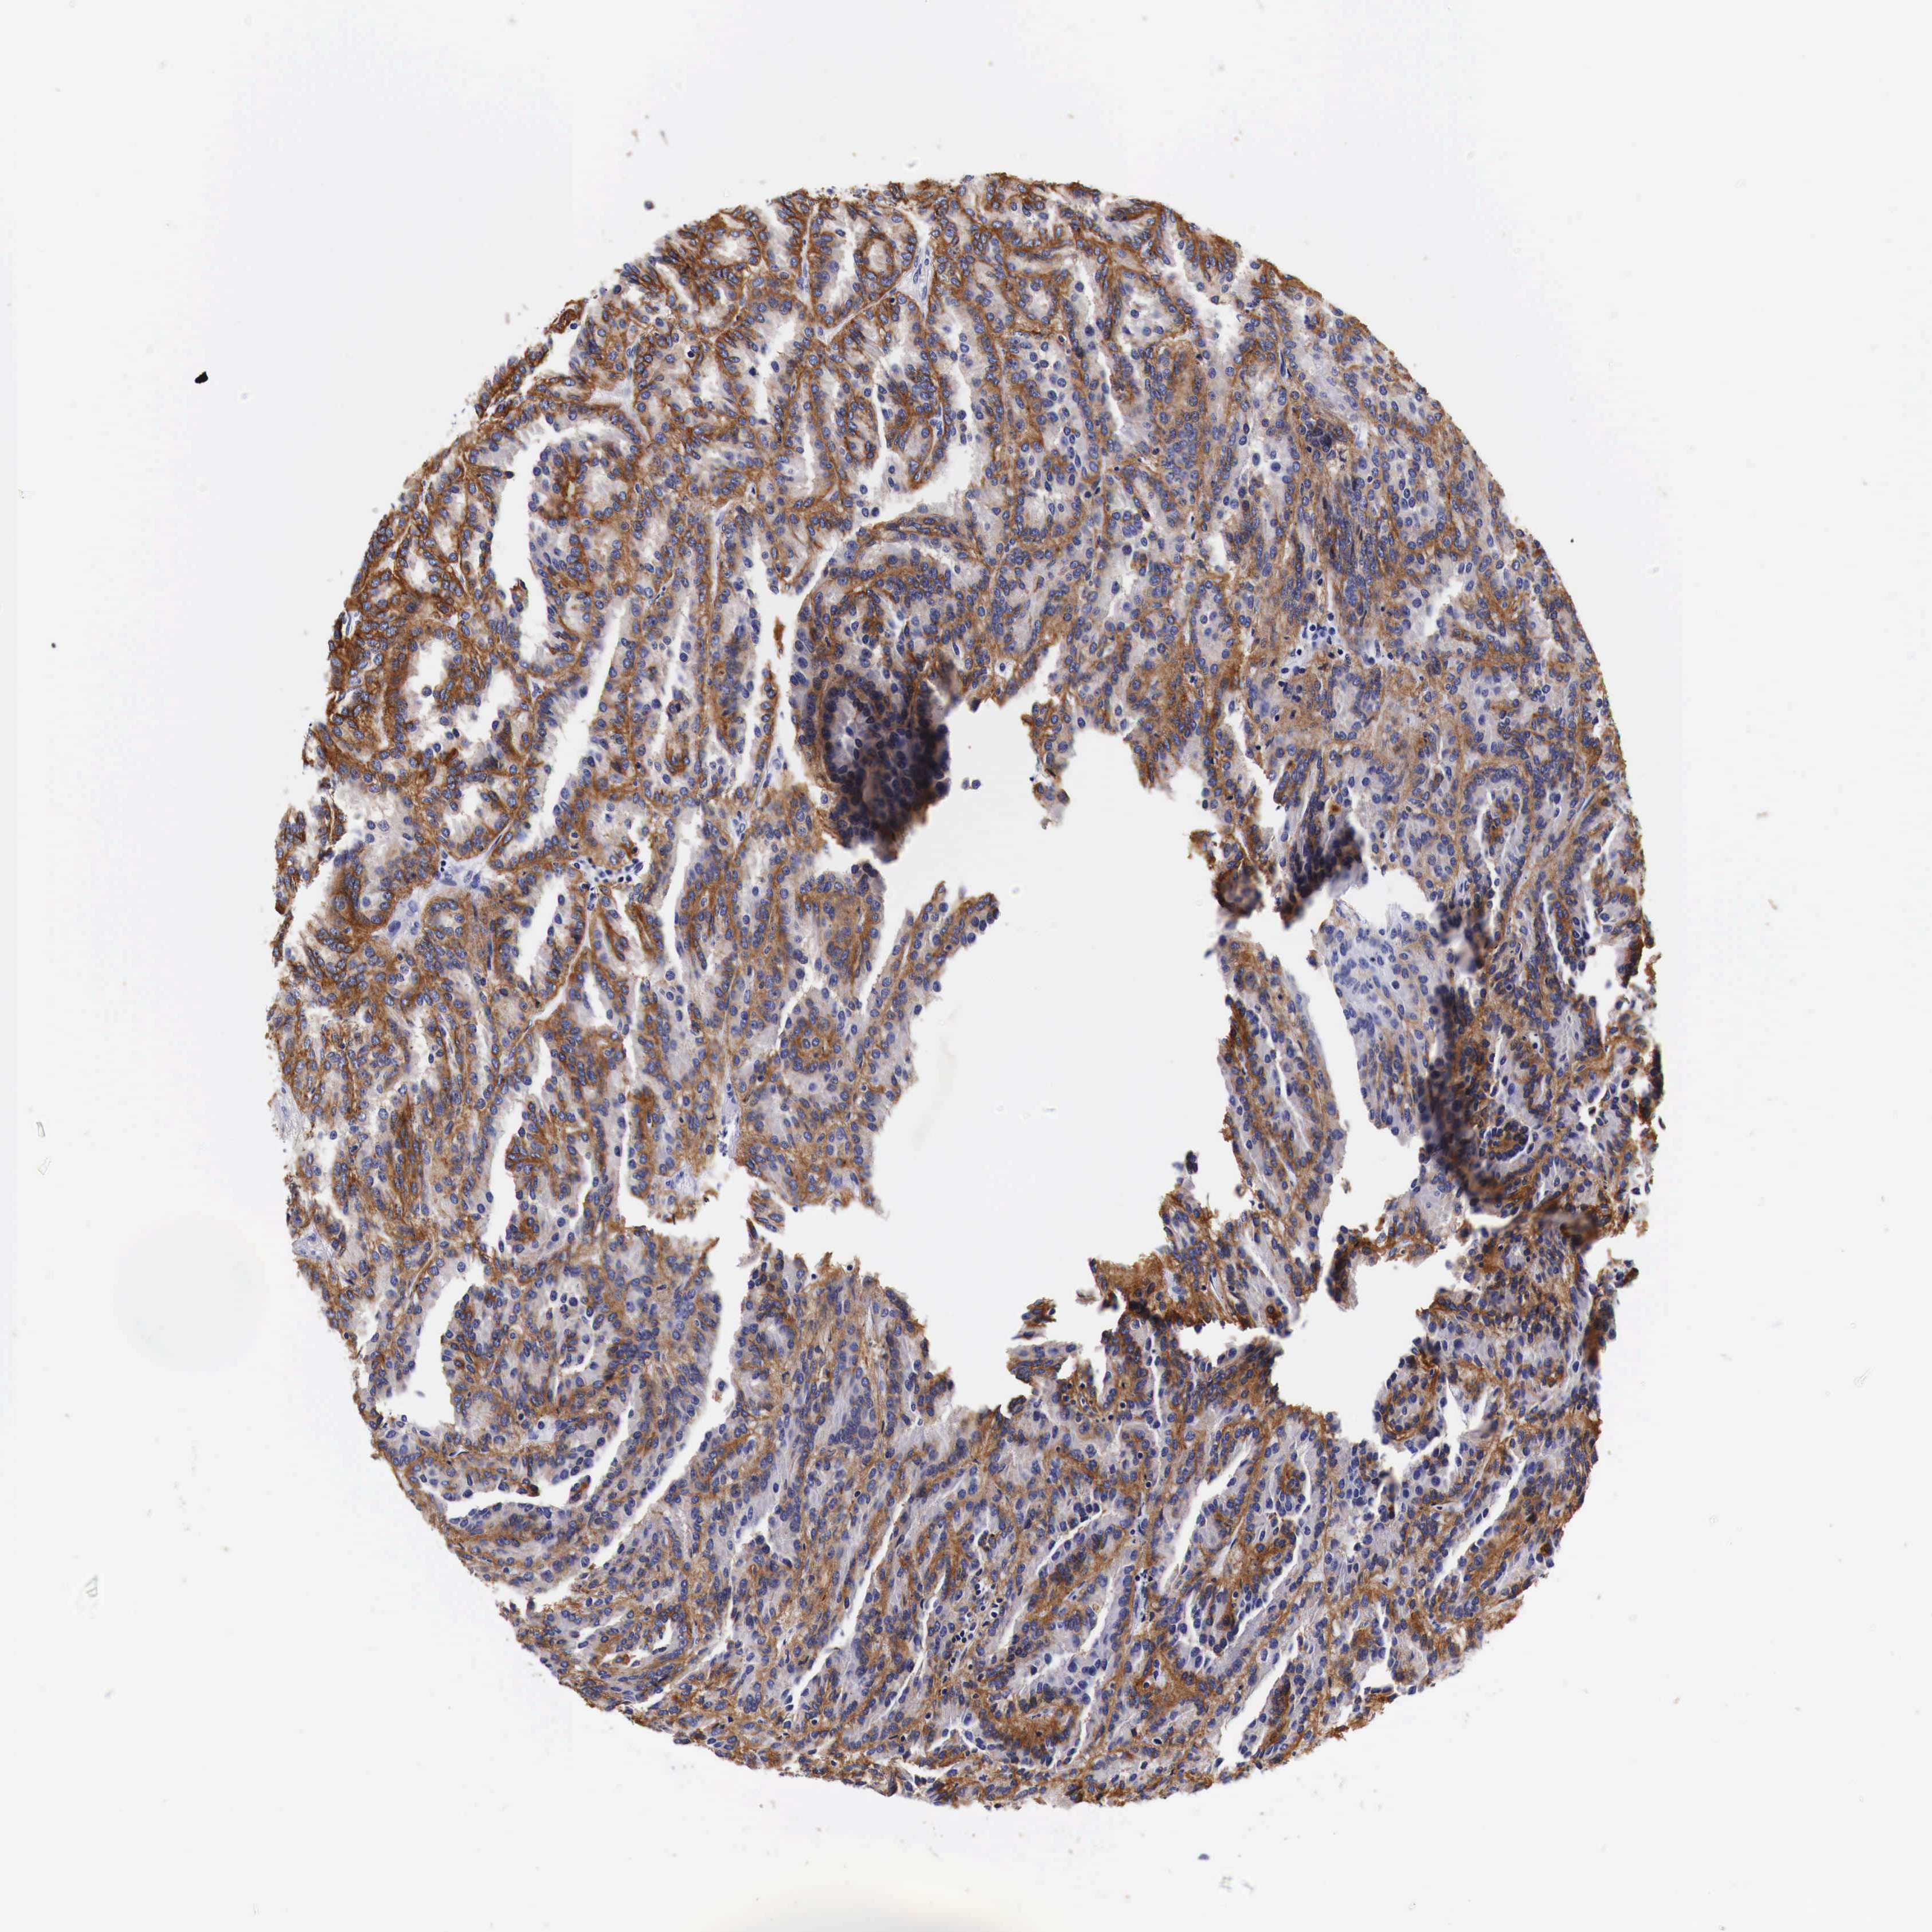

KIDNEY RENAL CLEAR CELL CARCINOMA (VALIDATION) - Interactive survival scatter ploti

The Survival Scatter plot shows the clinical status (i.e. dead or alive) for all individuals in the patient cohort, based on the same data that underlies the corresponding Kaplan-Meier plots. Patients that are alive at last time for follow-up are shown in blue and patients who have died during the study are shown in red.

The x-axis shows the expression levels (FPKM) of the investigated gene in the tumor tissue at the time of diagnosis. The y-axis shows the follow-up time after diagnosis (years). Both axes are complimented with kernel density curves demonstrating the data density over the axes. The top density plot shows the expression levels (FPKM) distribution among dead (red) and alive patients (blue). The right density plot shows the data density of the survived years of dead patients with high and low expression levels respectively, stratified using the cutoff indicated by the vertical dashed line through the Survival Scatter plot. This cutoff is automatically defined based on the FPKM cutoff that minimizes the p-score. The cutoff can be changed by dragging the vertical line or by entering a cutoff value in the square labeled "Current cut-off".

Under the Survival Scatter plot the p-score landscape (black curve; left axis) is shown together with dead median separation (red curve; right axis). Dead median separation is the difference in median mRNA expression between patients who have died with high and low expression, respectively. It is calculated as follows: median FPKM expression of dead patients with high expression - median FPKM expression of dead patients with low expression. This is intended to aid the user in visually exploring custom cutoffs and the associated p-scores and dead median separation.

Individual patient data is displayed and can be filtered by clicking on one or more of the category buttons on the top of the page. Categories describing expression level and patient information include: high, low, alive, dead, female, male and tumor stages. The scale of the x-axis can be toggled between linear and log-scale by clicking on the "x log" button. Mouse-over function shows TCGA ID, patient information and mRNA expression (FPKM) for each patient.

& Survival analysisi

Kaplan-Meier plots summarize results from analysis of correlation between mRNA expression level and patient survival. Patients were divided based on level of expression into one of the two groups "low" (under cut off) or "high" (over cut off). X-axis shows time for survival (years) and y-axis shows the probability of survival, where 1.0 corresponds to 100 percent.

EGFR is not prognostic in Kidney Renal Clear Cell Carcinoma (validation)

Best expression cut offi

Based on the FPKM value of each gene, patients were classified into two groups and association between prognosis (survival) and gene expression (FPKM) was examined. The best expression cut-off refers the FPKM value that yields maximal difference with regard to survival between the two groups at the lowest log-rank P-value. Best expression cut-off was selected based on survival analysis .

When clicking on this number, the vertical dashed line indicating cut-off, the interactive survival plot, and the Kaplan-Meier curve will be adjusted to show results based on the best expression cut-off.

: 44.55

P scorei

Log-rank P value for Kaplan-Meier plot showing results from analysis of correlation between mRNA expression level and patient survival.

N/A

TCGA RNA samplesi

RNA-seq data is reported as average FPKM (number Fragments Per Kilobase of exon per Million reads), generated by the The Cancer Genome Atlas (TCGA) .

Normal distribution across the dataset is visualized with box plots, shown as median and 25th and 75th percentiles. Points are displayed as outliers if they are above or below 1.5 times the interquartile range. FPKM values of the individual samples are presented next to the box plot.

Average pTPM 89.3

Number of samples 100